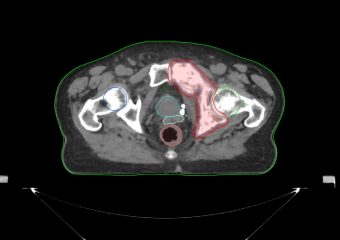

- 3D-CRT — трехмерная конформная лучевая терапия;

- IMRT — лучевая терапия с модуляцией интенсивности;

- VMAT — лучевая терапия с модуляцией интенсивности арками;

- IGRT — лучевая терапия с визуальным контролем;

- SBRT — стереотаксическая радиотерапия;

- SRS — стереотаксическая радиохирургия.

До процедуры производится подбор фиксирующих устройств, чтобы обеспечить неподвижность пациента во время лучевой терапии. Затем проводятся топометрические исследования и оконтуривание опухолевого очага. Планирование осуществляется на станциях Monaco, что позволяет оптимально распределить подводимую к опухоли дозу.

- Точная высокая доза излучения прицельно подается за короткое время. Аппарат дает возможность сформировать излучение, которое при распределении пучков будет точно соответствовать заданному объему – форме опухоли. Это позволяет избирательно облучать злокачественные очаги, щадяще обходя жизненно важные органы (сердце, печень, поджелудочная железа и др.).

- Перед сеансом лечения проводится всестороннее обследование: КТ, МРТ, ПЭТ-КТ, УЗИ и другие процедуры, назначенные лечащим врачом. Затем на аппарате TrueBeam выполняется визуальный контроль: пациент проходит сканирование, в результате которого врач получает данные об актуальном состоянии и положении опухоли, после чего процесс лечения может быть скорректирован и запущен с учетом новых данных. Улучшенный визуальный контроль позволяет точно контролировать процесс облучения без прерывания процедуры.